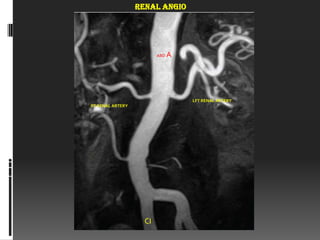

RENAL ANGIO

ABD   A

LFT RENAL ARTERY

RT RENAL ARTERY

CI